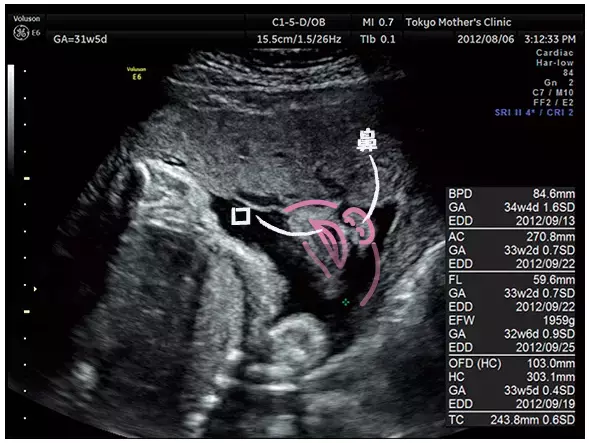

妊娠31週のエコー写真

赤ちゃんの顔を真下から見たところ。鼻の穴、口がひらいているところまで確認できる。

写真提供:東京マザーズクリニック